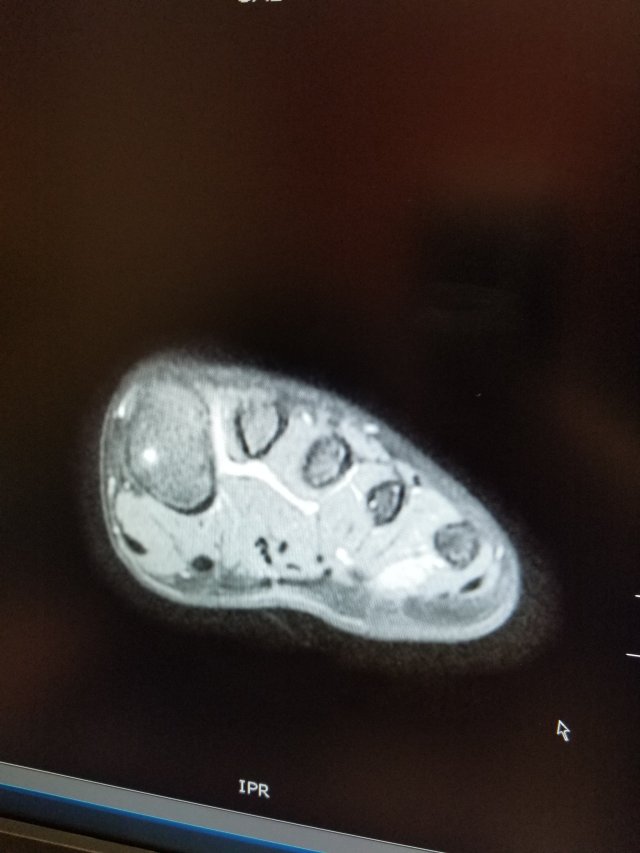

And one from a couple weeks ago:

The white blob between the 4th & 5th metatarsals is the tumor. Chemo has done a good job of shrinking it. Yay!

The surgeon will remove what’s left of it through the side of the foot. He’ll also remove some of the bone adjacent to the tumor.